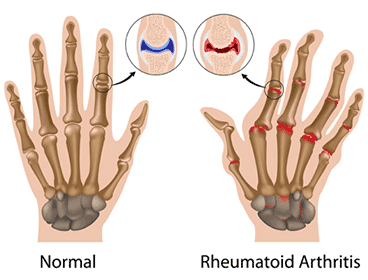

Ayurvedic treatment for arthritis

Ayurvedic treatment for arthritis focuses on reducing inflammation, detoxifying the body, and restoring joint mobility through herbal remedies, diet, and Panchakarma therapy.

Joint Pain

Ayurvedic treatment for joint pain focuses on reducing inflammation, strengthening bones and tissues, and restoring mobility through herbal oils, detox therapies, and lifestyle adjustments.

Arthritis

Ayurvedic treatment for arthritis aims to relieve joint pain and stiffness by balancing Vata dosha, reducing inflammation, and rejuvenating joints with herbs, diet, and Panchakarma therapy.